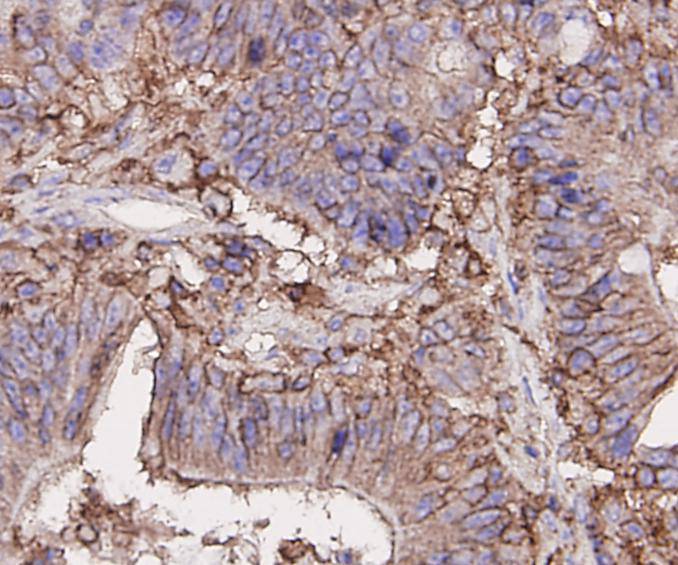

CD44 Mouse Monoclonal Antibody [A7-1]

IHC-P